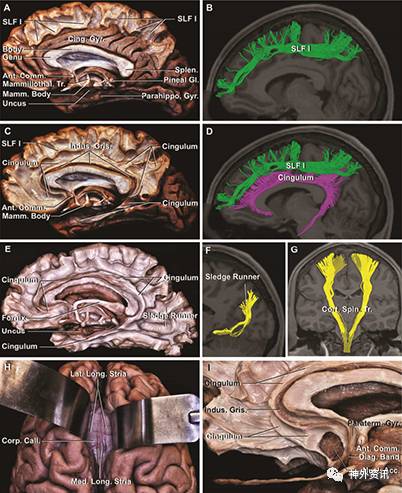

纤维束的解剖始于扣带沟,去除大脑内侧面额上回、旁中央小叶和楔前叶皮质,暴露U形纤维束。移除U形纤维,显露上纵束向前延伸,从楔前叶至内侧额叶。前扣带回皮质位于扣带和胼胝体纤维束上方。上纵束在DTI上呈波浪形结构(图2A-B)。去除扣带回背部到胼胝体的皮质,可见U形纤维束;除去U形纤维,暴露扣带束,显现大脑最长的纤维束联合。垂直纤维束从额上回、旁中央小叶和楔前叶进入扣带回束。在功能上,扣带束构成边缘系统背侧通路。旁中央小叶支配对侧下肢肌肉运动和膀胱功能,接受低级感觉神经传导(图2G)。在额叶区,扣带束在胼胝体膝部向下向后止于终板旁回和胼胝体下皮质;在顶叶,扣带束位于胼胝体背侧表面。去除海马旁回皮质暴露位于前下托和内嗅皮质的扣带回终止处(图2C-E)。去除楔叶和舌回皮质,显露位于距状裂深部的楔叶和舌回的白质纤维束(图2E-F)。内侧和外侧纵纹内有两对髓纤维束位于胼胝体背面和灰被下方。灰被进入Broca斜角带,成为杏仁核传出通路,从而构成终板旁回(图2C、2H、2I)。

图2. 右侧大脑半球内侧面纤维束解剖。